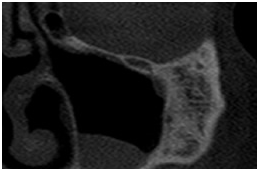

• Observar anomalias da ATM

Avaliação da ATM Avaliação da ATM